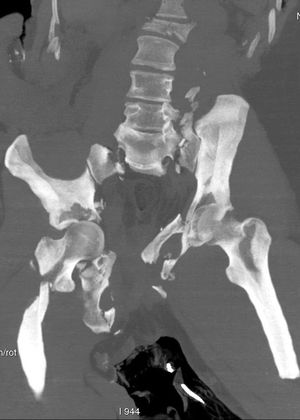

CAT Scan of lower thoracic and pelvic region of aviation accident victim who died of massive blunt trauma prior to fire caused by crash. One of the primary ways that medical investigators can determine whether or not a cadaver found in a fire scene died as a result of the fire is by examining the airways. If soot is found in the lungs, that means that they inhaled smoke, and were alive when the fire started.